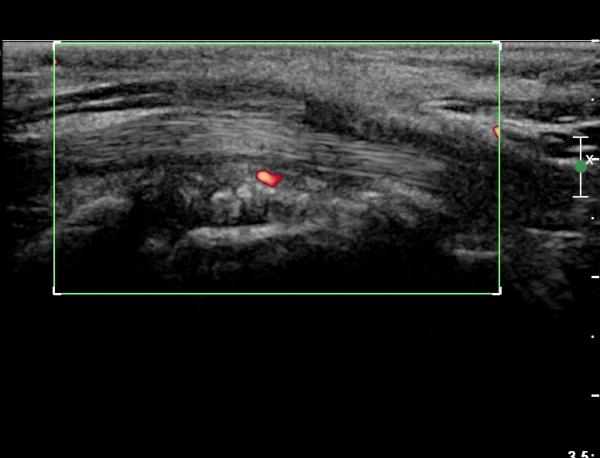

ÈûÁÙ ¹× Á¤Á߽ŰæÀÇ Ç¥ÃþÀ¸·Î ÀüÀ§°¡ °üÂûµÈ´Ù, (»çÁø 1 ), ÆÄ¿öµµÇ÷¯°Ë»ç¿¡¼ Ç÷·ùÁõ°¡°¡ °üÂûµÊ´Ù(»çÁø 2)..